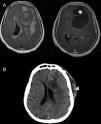

Patients and methodsSix patients with cystic meningiomas were included in the study. All patients underwent a cranial computed tomography scan and magnetic resonance imaging (MRI) evaluation, pre- and postoperatively.

ResultsAll patients presented with long standing headache dating back at least two years. There was no gender predominance in our series. Radiological evaluation revealed two parasagittal and two convexity meningiomas located at the frontal region. Two lesions were located at the tuberculum sellae and the foramen magnum. All of the tumors were totally excised (Simpson Grade I or II). Pathology results included meningothelial meningioma in three patients, angiomatous meningioma in two patients, and metaplastic meningioma in one patient. In two patients, the cystic meningiomas were resected with the use of sodium fluorescein (Na-Fl) under a YELLOW 560nm microscope filter. Na-Fl was found to be very useful in demonstrating the brain–tumor interface, and it was especially effective in resecting the cyst wall of the peritumoural cystic meningiomas. None of the patients had any complications, and no recurrences were noted in any of the patients within the mean follow-up period of 51 months (range: 16–102 months).